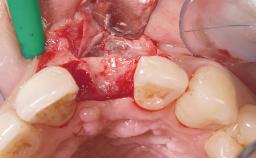

Immediate Placement of an Implant in a Maxillary Right Central Incisor Site

A 30-year-old female patient was referred to the office for the treatment of tooth 11. Her chief concern at the initial visit was to inquire, “Why is my tooth pink?” Upon clinical examination, it was determined that tooth 11 had a previous history of trauma and that the clinical crown had become noticeably pink in color as a result of internal resorption. This diagnosis was confirmed radiographically, indicating a large radiolucency involving the central and distal portions of the clinical crown. It was determined that restoration of this tooth was not possible, and that extraction was indicated. The presence of a mid-line diastema, which the patient wanted to reproduce, directed the treatment plan for tooth replacement utilizing a dental implant.

| Bone Augmentation | Horizontal|Simultaneous |

| Augmentation Materials | Autogenous chips|Membrane |

| Placement Protocol | Immediate implant placement |

| Tooth Site | Maxillary incisor or canine |

| Socket Morphology | Single-root socket |

| Socket Integrity | Sufficient, with intact bone walls |

| Bone Volume | Sufficient, with intact walls |